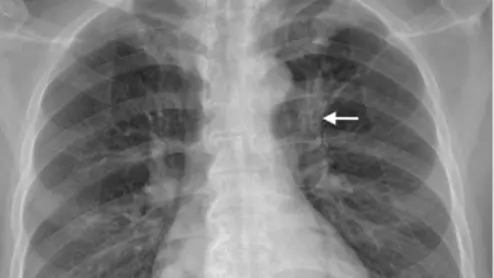

lung cancer imaging features associated with worse outcomes following missed diagnosis

Features pertaining to location, density and superimposed structures were recently found to be associated with poorer outcomes for patients who initially had their lung cancer overlooked on radiographs.